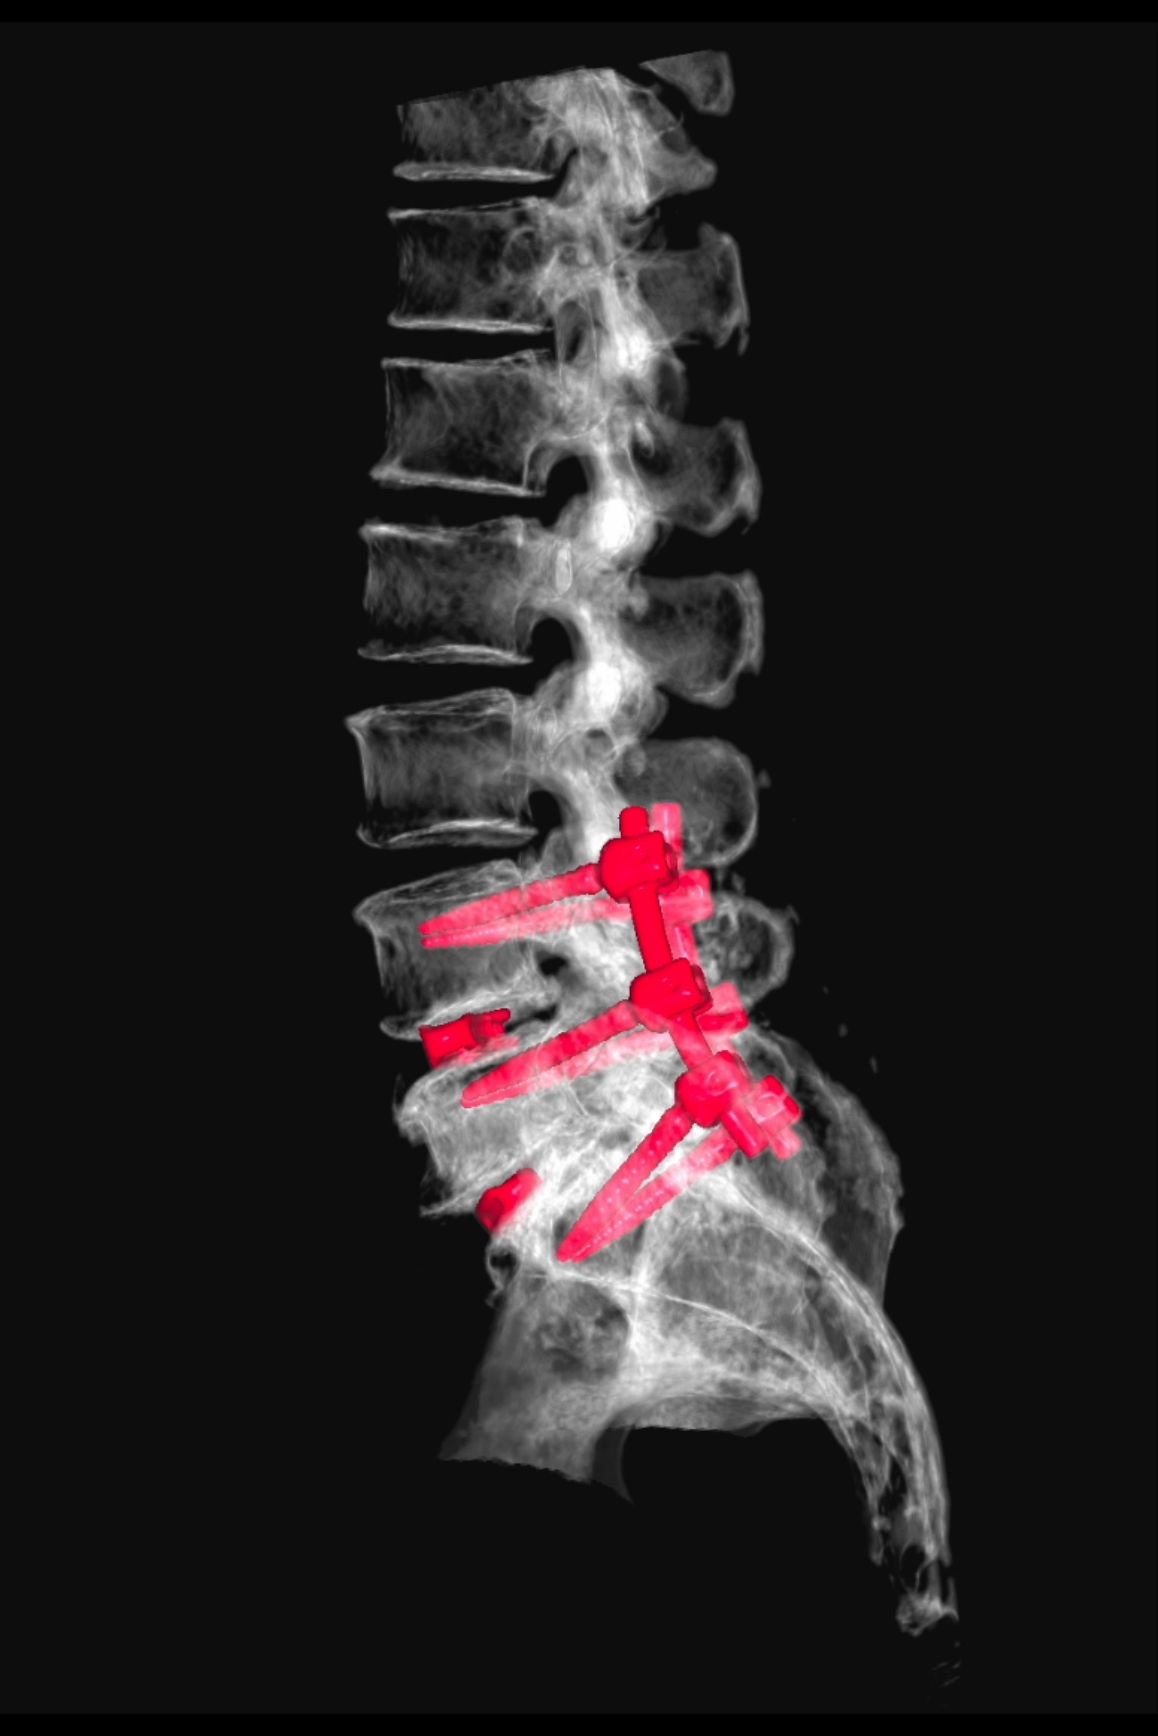

• Cirugía de columna vertebral y tratamiento de hernia lumbar y cervical

• Cirugía de columna mínimamente invasiva

Desde $80,000